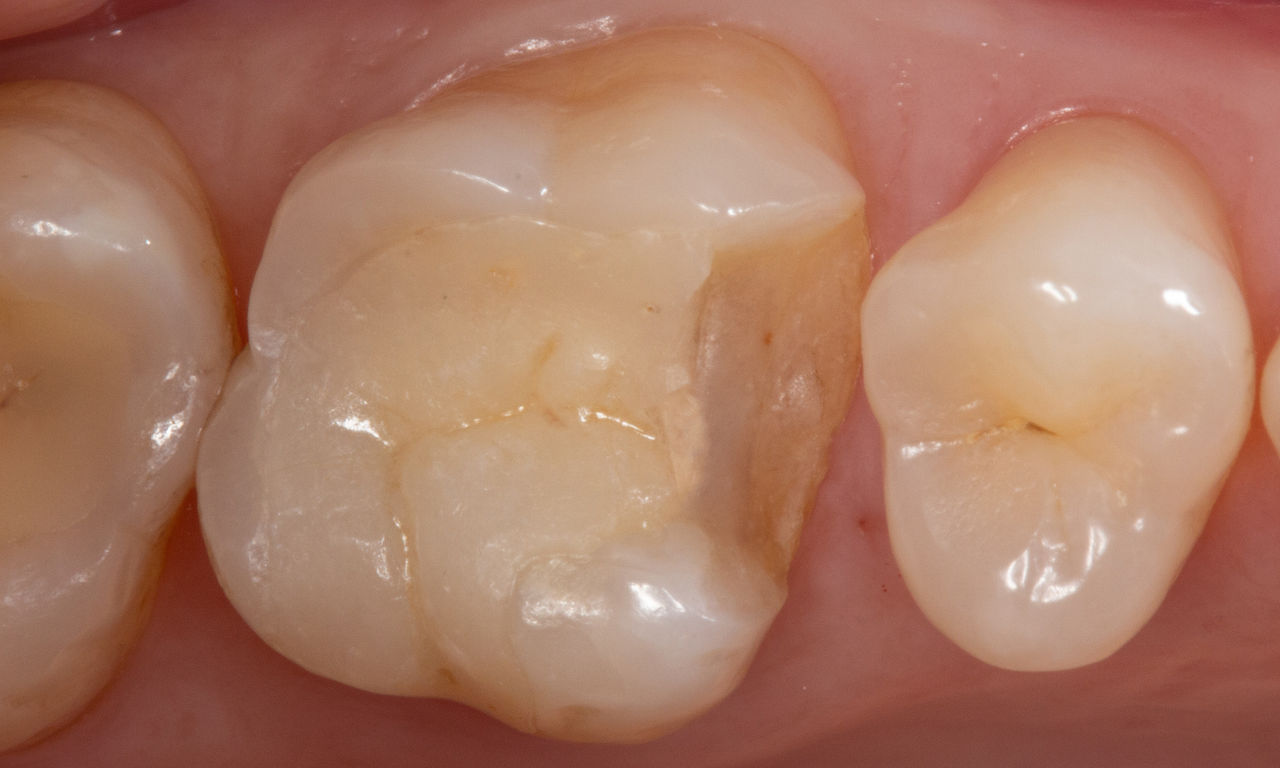

Before

First upper molar had been restored with an extensive yet insufficient composite filling that already showed visible fractures.

After

Chairside-fabricated restoration made from an advanced lithium disilicate ceramic, CEREC Tessera.